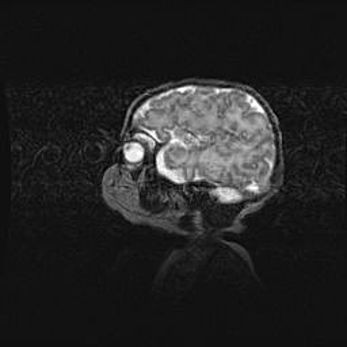

Лейкомаляция с кистозно-глиозной дегенерацией головного мозга.

Возраст: 2 месяца 25 дней

Вес: 6400 г

Окружность головы: 40 см

Срок гестации: 41 неделя

Лейкомаляцию относят к ишемически-гипоксическим повреждениям головного мозга, диагностируемым у новорожденных. При лейкомаляции в головном мозге обнаруживают очаги некроза, возникшие после тяжелой гипоксии и нарушения кровотока. В процессе морфогенеза очаги проходят три стадии: 1) развития некроза, 2) резорбции и 3) формирования глиозного рубца или кисты. Перивентрикулярная лейкомаляция (ПЛ) встречается примерно в 12% случаев среди новорожденных, обычно – у недоношенных детей, причем, частота ее зависит от массы, с которой младенец появился на свет. Наибольшее число малышей страдает лейкомаляцией, если масса при рождении 1500-2500 г.